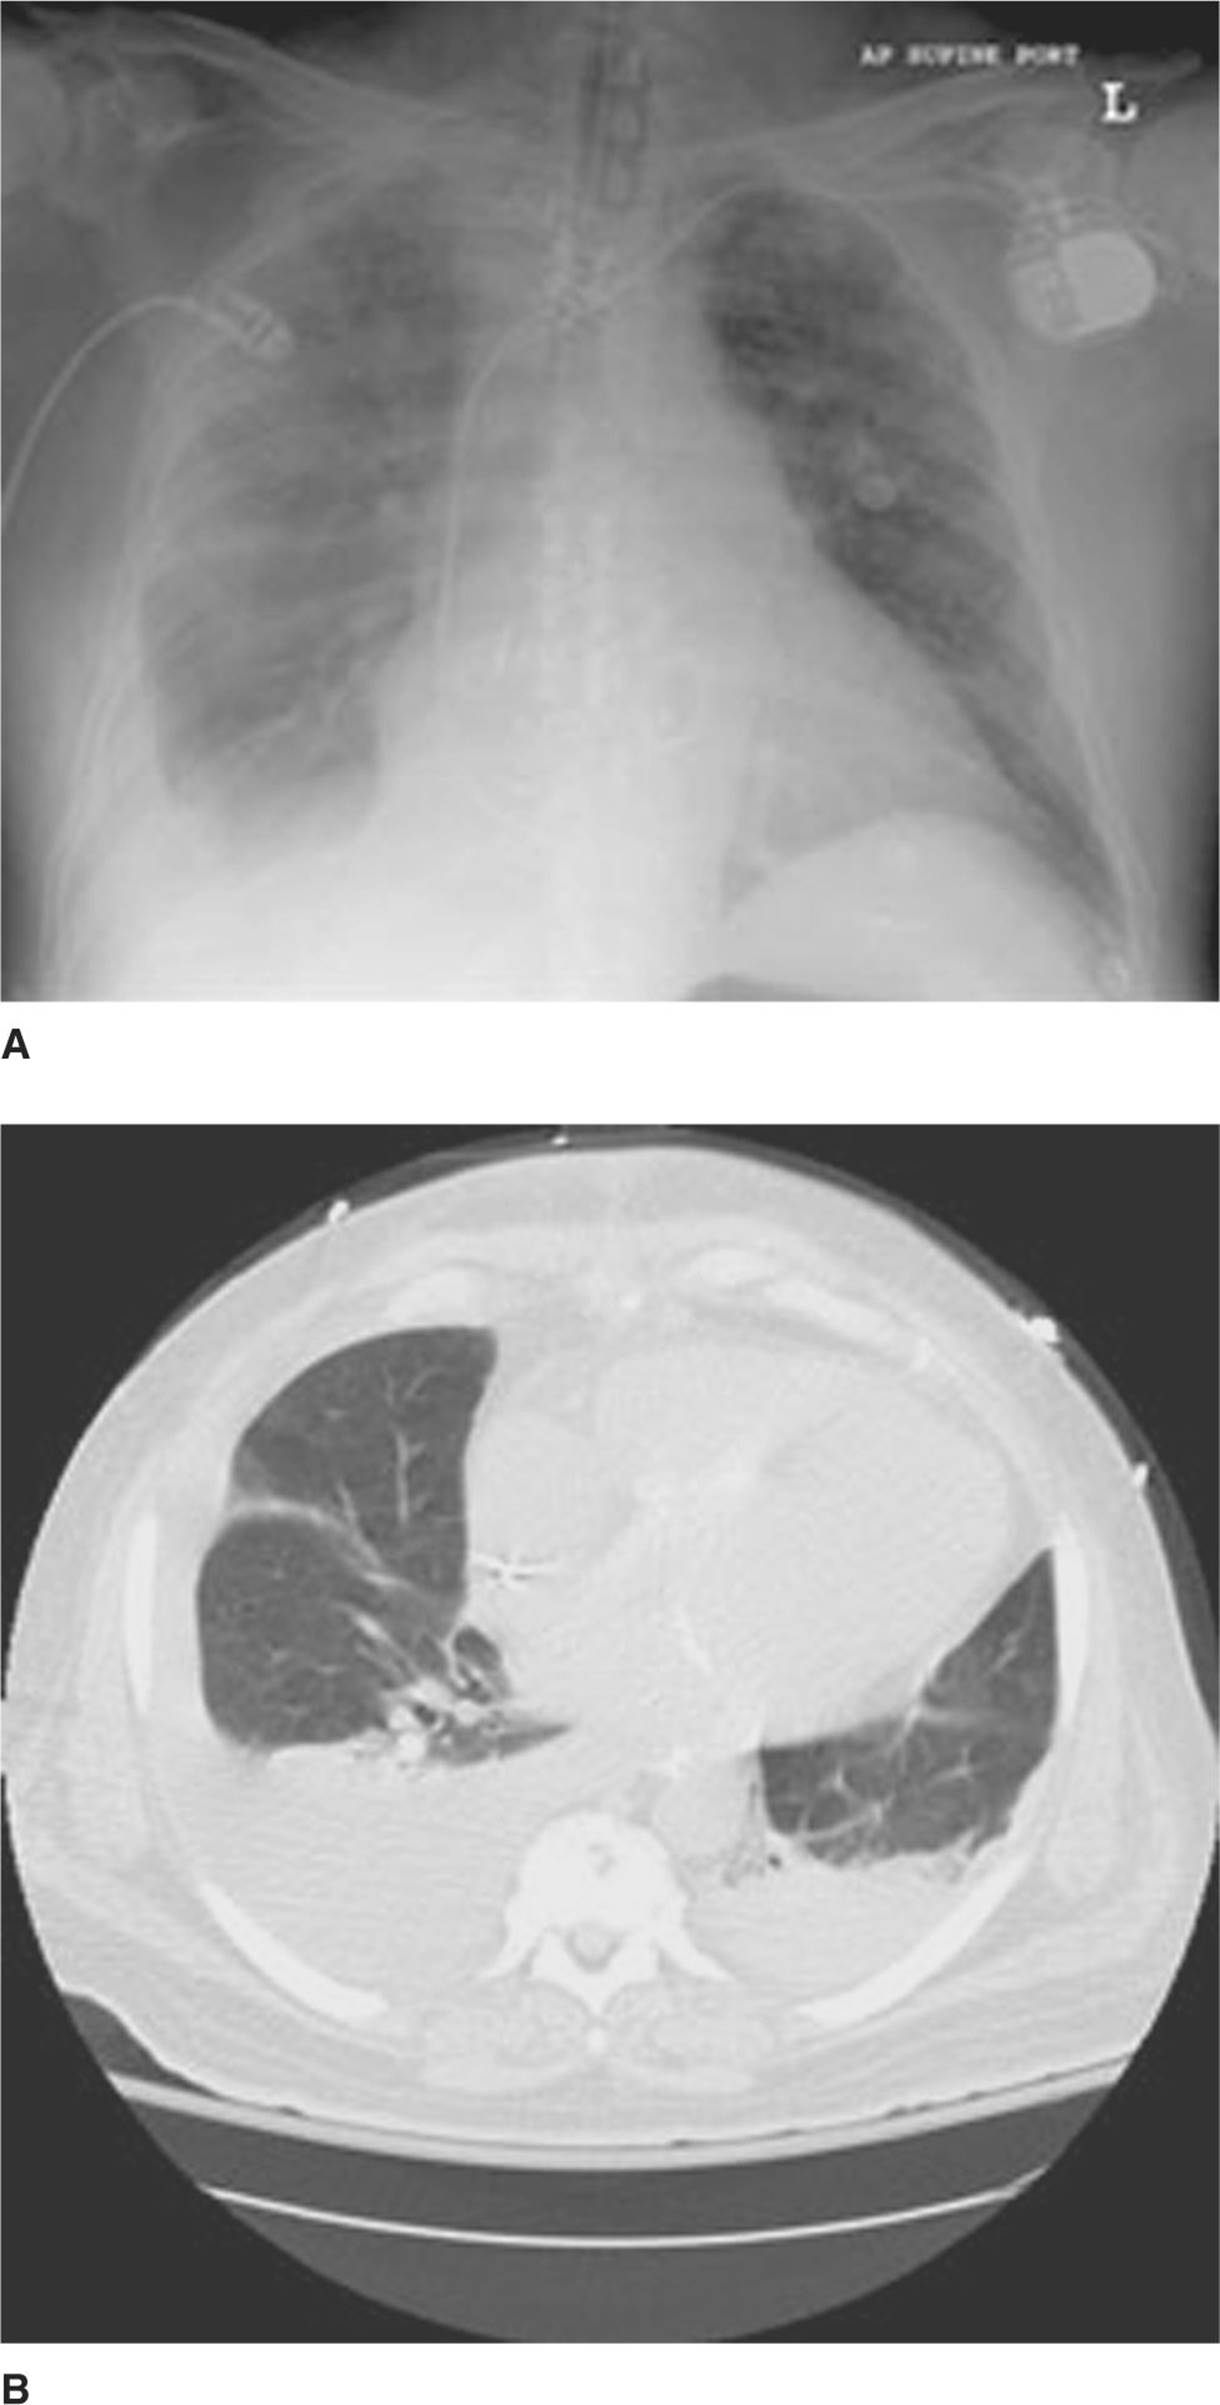

Approximately 150 to 200 mL of pleural fluid are required to identify an effusion on upright CXR (see Fig. 31-1).

Significant pleural effusions will be large enough to produce a >10-mm strip on a lateral decubitus CXR, or on thoracic ultrasound.

FIG. 31-1. A. This is a supine radiograph showing a right-sided pleural effusion. The right lung field is hazy compared to the left, and a small layer of fluid is noted inferiorly. B. CT scan of the patient in (A). A moderate pleural effusion is noted in the right lung field, and a small effusion not seen in the left lung field of the plain film is noted on the CT scan.